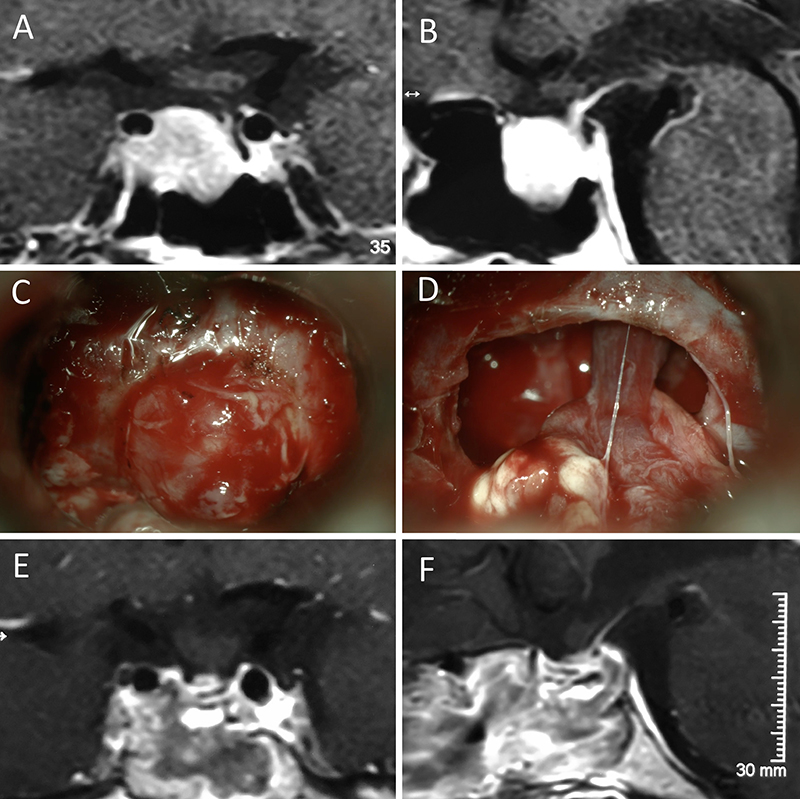

Figura 1: Macroadenoma no funcionante en mujer de 65 año

s. Se decidió la cirugía tras evidenciarse crecimiento en los controles. Evolucionó favorablemente desde el punto de vista clínico-radiológico. A-B: RM preoperatoria; C-D: intraoperatorio; E-F: RM postoperatoria.

Figura 2: Macroadenoma no funcionante en mujer de 31 años. La paciente presentó en el preoperatorio déficit visual que mejoró tras la cirugía. A-B: RM preoperatoria; C-D: intraoperatorio; E-F: RM postoperatoria.

Figura 3: Macroadenoma no funcionante en un hombre de 64 años. El paciente presentó en el preoperatorio déficit visual que mejoró tras la cirugía. A-B: RM preoperatoria; C-D: intraoperatorio; E-F: RM postoperatoria.

Figura 4: Macroadenoma no funcionante en mujer de 32 años. La paciente presentó en el preoperatorio déficit visual que mejoró tras la cirugía. A-B: RM preoperatoria; C-D: intraoperatorio; E-F: RM postoperatoria.

Figura 5: Apoplejía hipofisaria hemorrágica en un hombre de 32 años. El paciente presentó cefalea y parálisis completa del III par. Tuvo restitutio ad integrum en el seguimiento. A-B: RM preoperatoria; C-D: intraoperatorio; E-F: RM postoperatoria.

Figura 6: Apoplejía hipofisaria hemorrágica en un hombre de 55 años. El paciente presentó cefalea, déficit visual y parálisis completa del III par. Evolucionó favorablemente tras la cirugía, revirtiendo el cuadro. A-B: RM preoperatoria; C-D: intraoperatorio; E-F: RM postoperatoria.